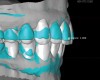

For dental implant-based treatment, the planning phase begins with collection of basic data sets; this is digital touchpoint 1. It includes: (1) a cone-beam CT (CBCT) to view edentulous areas or failing tooth structure, bone, and anatomic landmarks under the soft tissue (Figure 2 through Figure 4); and (2) an intraoral optical scan (IOS) or a scanned model or impression to record the soft tissue and tooth anatomy (Figure 5). The superimposition of the digital imaging and communications in medicine (DICOM) files from the CBCT and the standard tessellation language (STL) files from the IOS allows visualization of how bone, dental structures, and soft tissues relate. Both digital data points are key to implant selection and determining the surrounding bone-grafting needs. An initial treatment plan includes determining the desired implant manufacturer/implant design, size, and positions; these decisions remain the responsibility of the clinician (restoring and surgical team members) and not the technician or planning team.

To fully understand how the digital process benefits any form of treatment planning (eg, teeth or implants or a combination), it is helpful to work with systems that can handle precise data that includes the face and smile as a framework. Procedure-specific methods, such as "smiling scan techniques," have been described that bring into focus the importance of facially planned and driven surgical and prosthetic steps.6,7 For this article, the authors use a planning system (Face Hunter scanner, Zirkonzahn, zirkonzahn.com) that allows the creation of a "virtual patient" by creating a photorealistic 3D digitalized face that serves as a working basis for the production of dental prostheses. This program and tooling are primarily utilized in laboratories, but these types of planning and milling/printing systems may become more prevalent in high-volume dental clinics. Use of this type of digital platform versus conventional prosthodontic methods in the planning and execution of treatment strengthens the esthetic and functional value of the intraoral data from digital touchpoint 1. The steps in the aforementioned planning system protocol include: